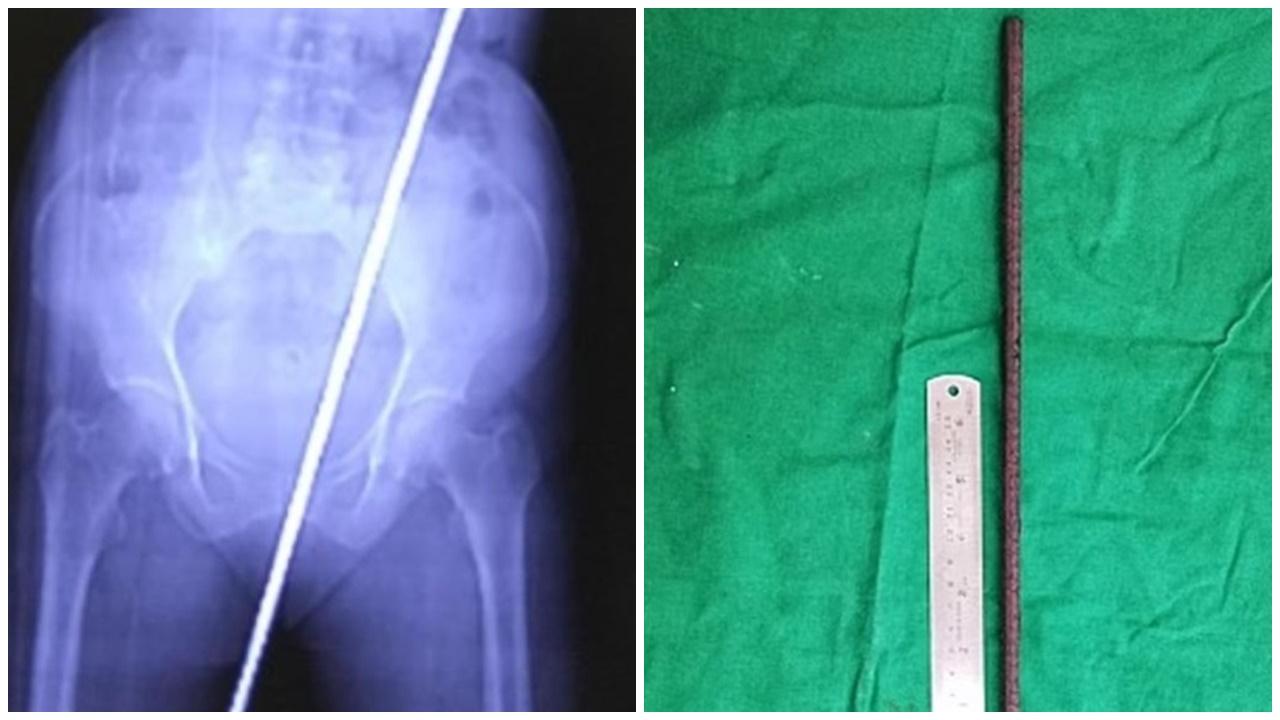

• 婦人一跌慘被2呎長鐵棍貫「後門」,牛屎鐵鏽入肚。(網上圖片)

婦人一跌慘被2呎長鐵棍貫「後門」 牛屎鐵鏽全入肚

國際

1年前